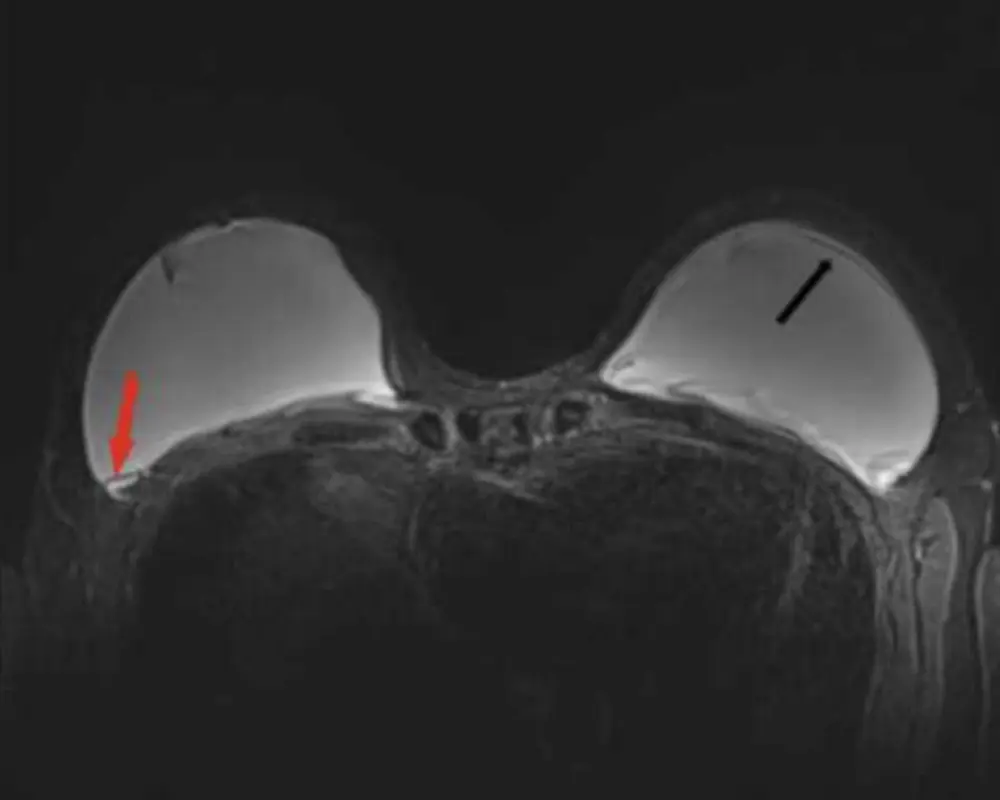

Breast Implant Evaluation

Breast MRI helps evaluate breast implants by detecting ruptures, leaks, or structural issues. It provides detailed imaging to assess implant condition and supports accurate diagnosis when patients experience discomfort or changes.

Implant Concerns

Those with breast implants may require a breast MRI to check for rupture, leakage, or structural changes. It provides detailed imaging to assess implant condition and surrounding tissue accurately.